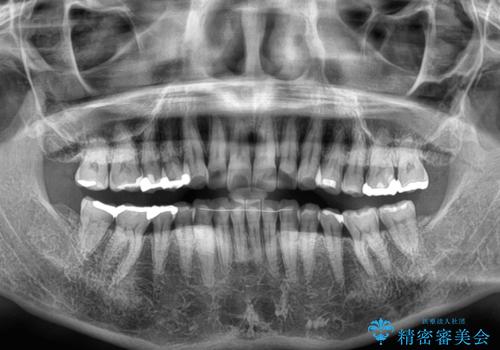

- 前歯のデコボコと上下正中のずれを気にして来院された患者様です。

下顎骨が骨格的にずれがあったため、しっかりと正中を合わせるとなるとワイヤー矯正が必要でしたが、マウスピース矯正を希望されたため、極力正中を合わせることを目標に、インビザラインにて矯正治療を行うこととしました。